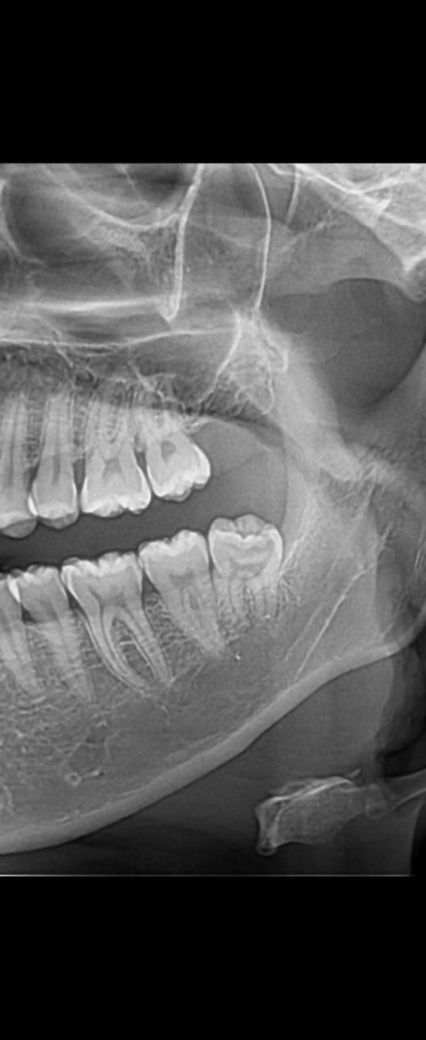

사랑니 발치 질문합니다. 엑스레이 사진 첨부해서요 ?

교정을 위해 사랑니를 뺴려고 합니다... 찾아보니 사랑니는 잇몸을 쨰고 뺴면 마취 풀린후 통증이 매우 심하다고 다들 그러네요..

저는 잇몸을쨰고 빼야하는지 궁금합니다. 나이는 25살 남자입니다.

잇몸 굳이 안째고도 빼는 것 가능할 것 같습니다

잇몸을 째야 하는 케이스는 발치 기구가 치아 풍융부(불룩한부분) 직하방으로 들어가지 못해 지렛대 원리를 이용하지 못하는 경우입니다

이미 사랑니가 나와 있는 상황에서는 잇몸을 절개하지 않고 발치가 가능합니다.

잇몸을 절개 하지 않고 발치를 해되 될것같습니다. 크게 통증이 잇을 사랑니는 아니니 너무 걱정하지마세요.